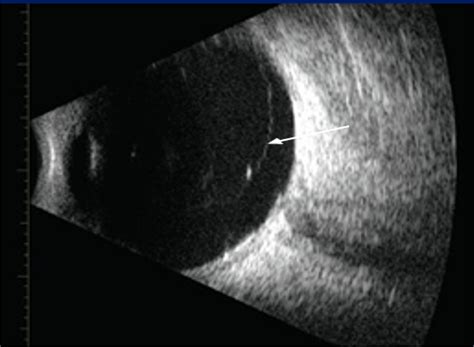

Upon visiting an ophthalmologist or retina specialist, the doctor will dilate your pupils to get a clear view of the entire retinal surface. They use specialized lenses to examine the peripheral retina where tears are most likely to occur. If a tear is detected, the specialist will determine whether it requires immediate stabilization. The retinal tear prognosis is significantly better if the tear is caught before it progresses to a full retinal detachment—a condition where the retina completely peels away from the wall of the eye.

Once a tear is identified, treatment is generally non-invasive compared to surgery for detachment. The goal of treatment is to “weld” the retina back to the underlying tissue to prevent fluid from seeping behind it. The most common procedures include: